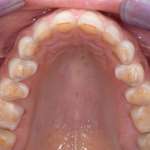

Riabilitazione adesiva minimamente invasiva di arcate con estesa usura dentale Premium

Viene presentata una metodica per la ricostruzione diretta di elementi con severa usura dentale che permette, nella fase preliminare, di verificare l’accettabilità da parte del paziente delle modifiche occlusali che verranno apportate. Viene riportata l’analisi retrospettiva di 20 casi con un follow-up di sei anni